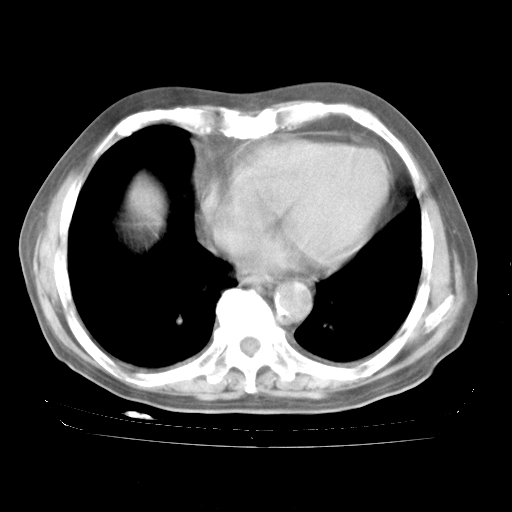

4月28日肺部CT——再次出现类似去年5月9日——磨玻璃样、间有“粟粒样”改变。

4月28日肺部CT